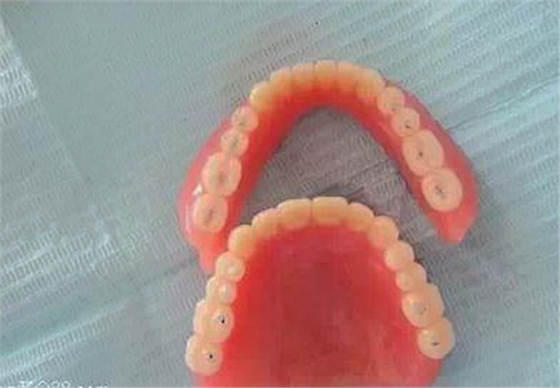

這是我用長(zhǎng)正中合型修復(fù)的全口義齒。

排牙時(shí)嚴(yán)格按照步驟進(jìn)行,咬合接觸點(diǎn)很接近書(shū)上的要求。

制作完成的義齒。